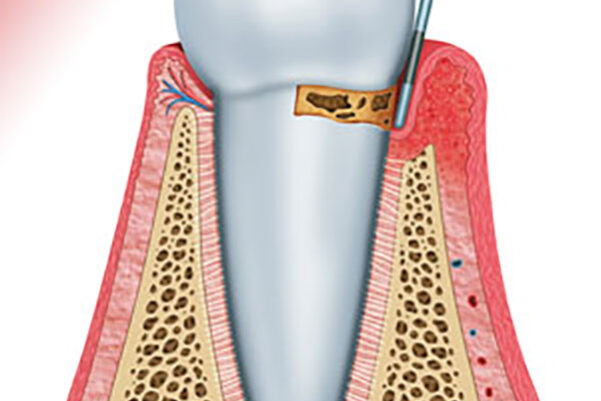

La periodoncia previene y trata las enfermedades que afectan a los tejidos que soportan los dientes, siendo la gingivitis y la periodontitis las más comunes.

En caso de gingivitis no tratadas, nos encontramos con grados más severos de patología periodontal (periodontitis), aumentando el riesgo de pérdida de soporte óseo de los dientes, lo que conlleva a movilidad dental o pérdida de piezas dentales.